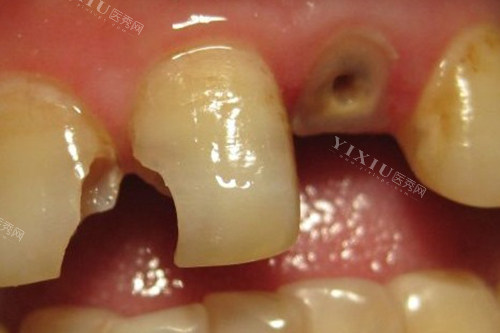

对于大牙被蛀空的问题,建议您尽快就医,以免病情进一步恶化。蛀空是指牙齿表面出现洞穴或部分被破坏,这可能会导致食物残渣积聚、疼痛、感染等问题。在金昌,针对大牙蛀空的情况,常见的治疗方法包括:

牙齿补缺:根据蛀空的程度,牙医会使用相应的材料(如树脂、陶瓷等)进行填充修复,以恢复牙齿形态和功能。补牙是治疗大牙蛀空常见的方法,也是更经济实惠的选择。

牙齿牙冠修复:如果蛀空程度比较深,补牙成效不佳,牙医可能会推荐牙冠修复,将感染部分清除,然后在根据剩余牙体部分进行个性化定制牙冠,从而修补牙齿以达到美观和功能恢复的目的。

牙齿根管治疗:当大牙蛀空程度到影响牙髓(牙齿内的组织)时,可能需要进行根管治疗。根管治疗是将受损或感染的牙髓清除并用特殊材料填充,以挽救牙齿并预防进一步感染。